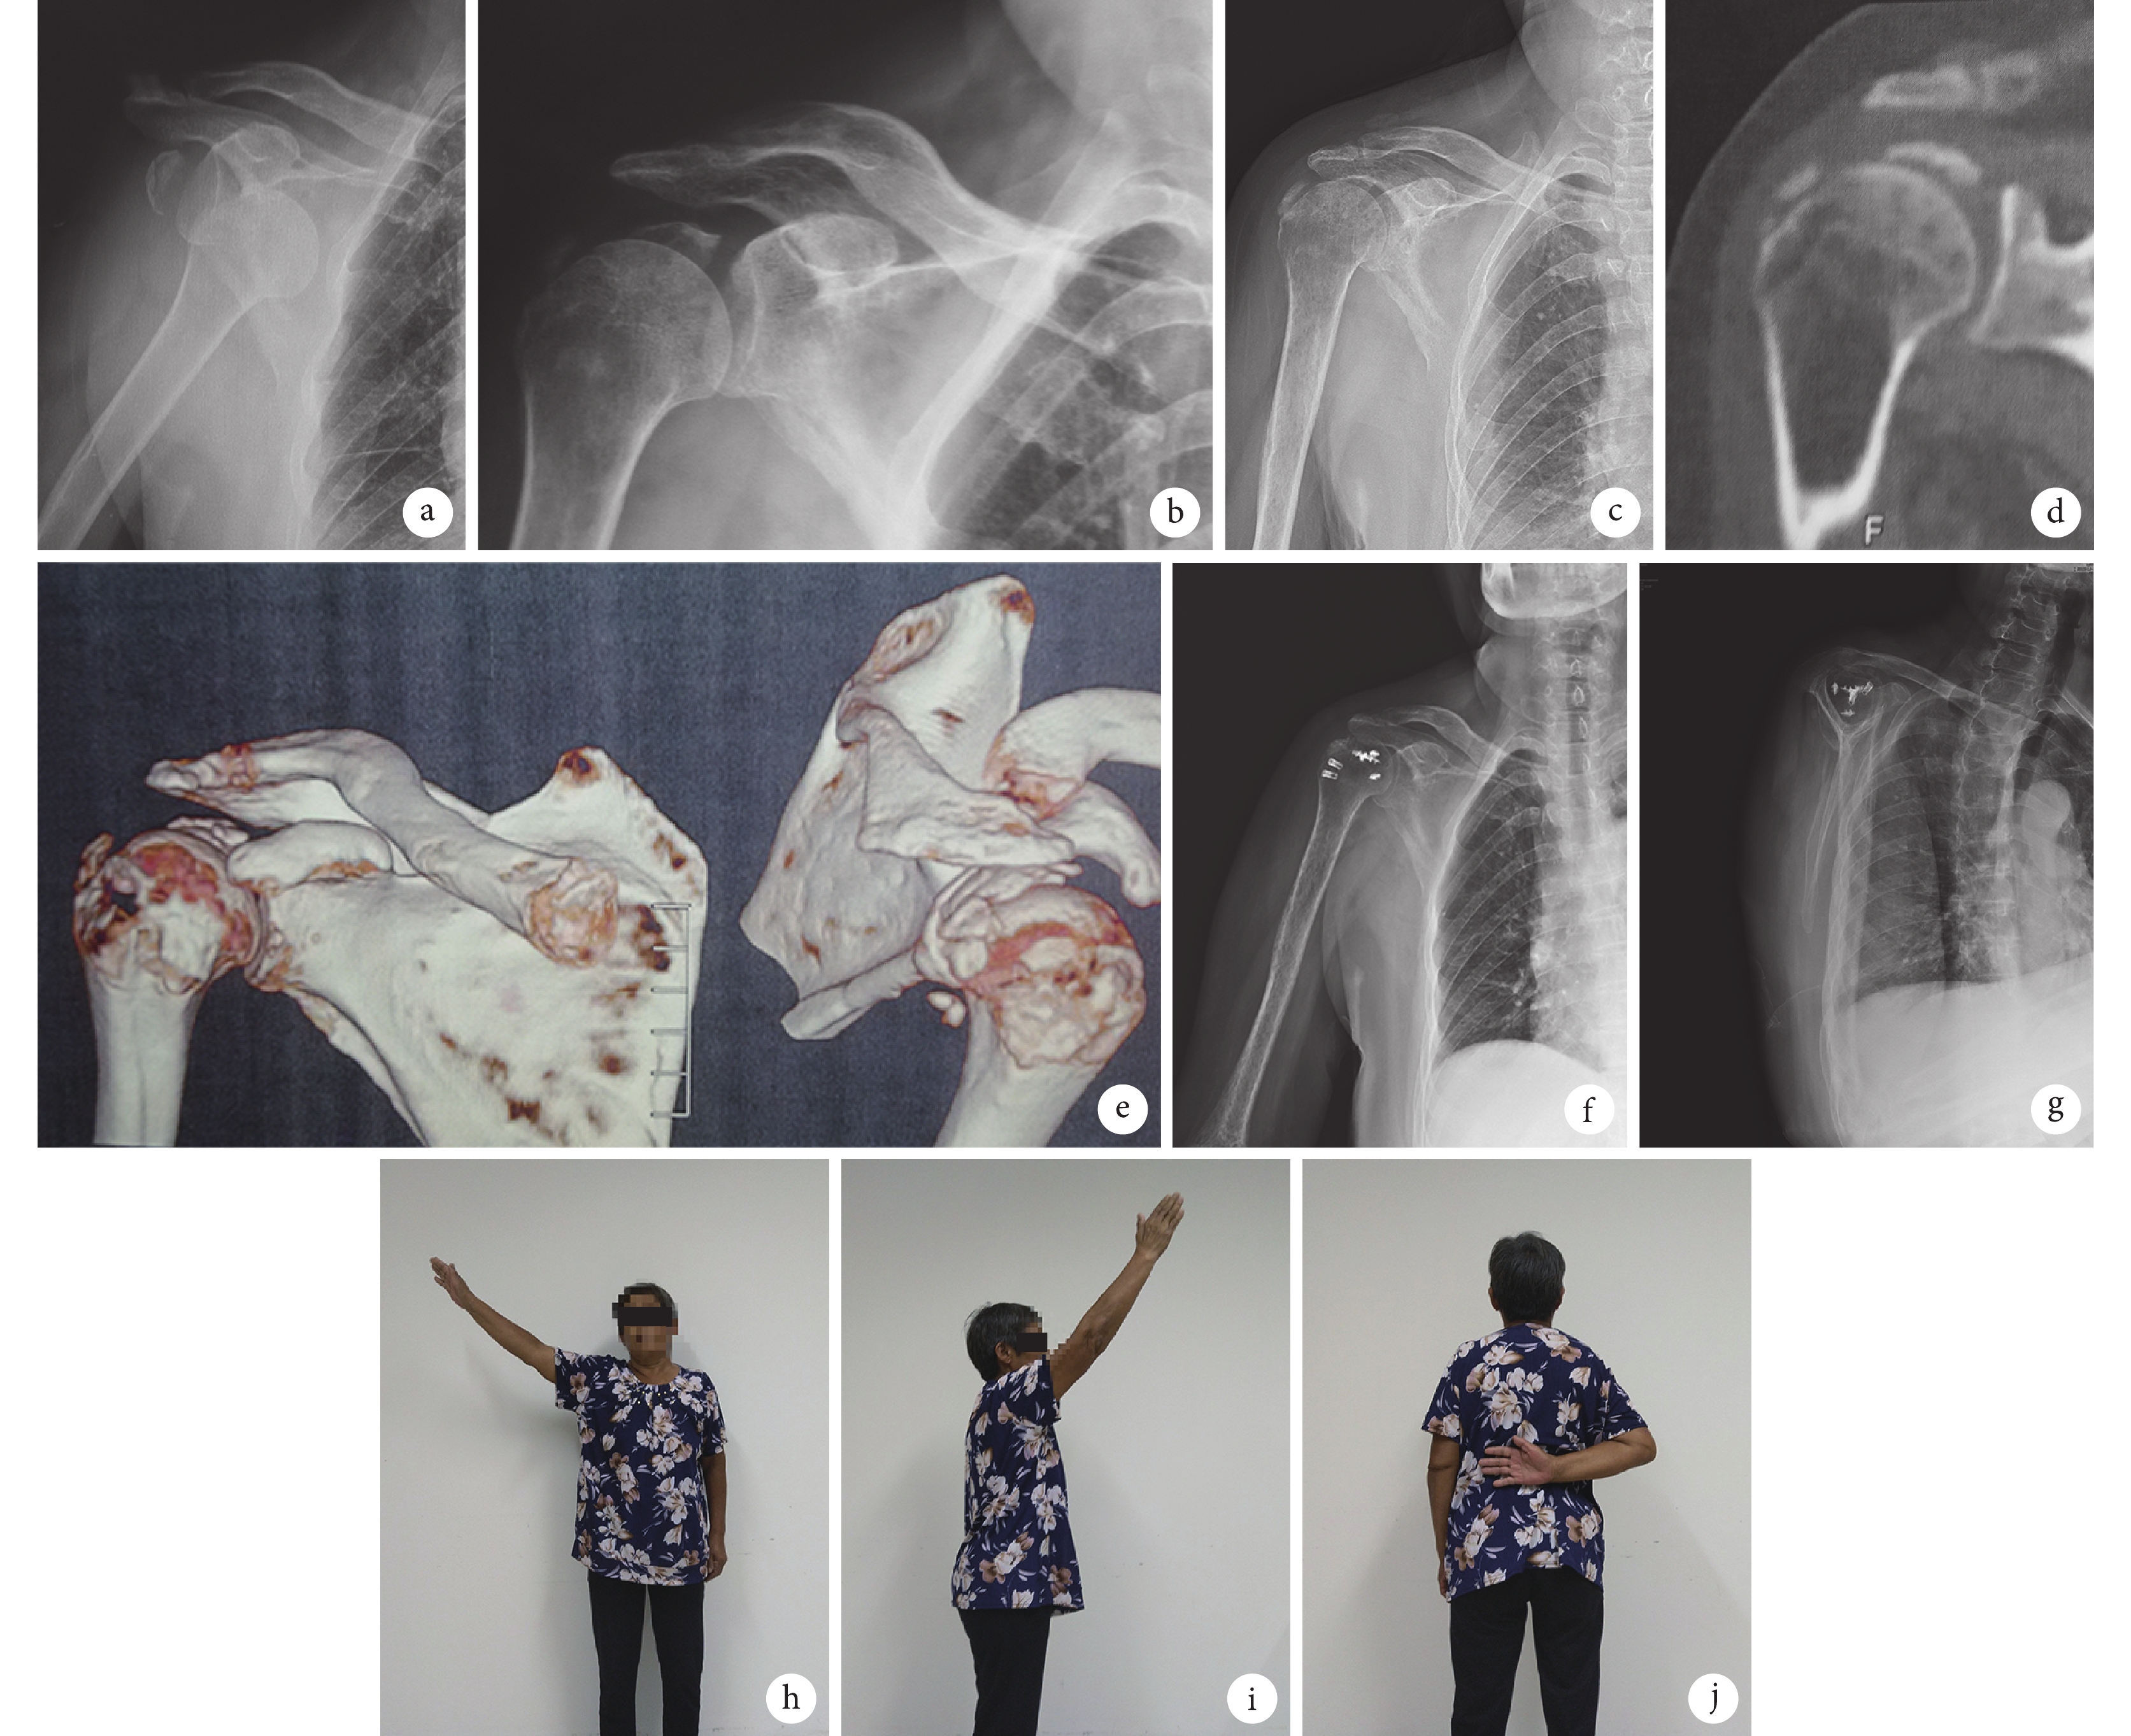

患者,女,66歲,交通事故傷致右側盂肱關節前脫位、肱骨大結節骨折,閉合復位3個月后,右肩關節仍疼痛、活動受限,行手術治療

a. 閉合復位前 X 線片;b. 閉合復位后 X 線片;c~e. 術前(閉合復位后 3 個月)X 線片及 CT;f、g. 開放復位內固定術后 3 個月 X 線片;h~j. 術后 9 個月肩關節功能

Figure1. A 66-year-old female patient with anterior dislocation of the right glenohumeral joint and fracture of great tuberosity by a traffic accident, who was treated with operation at 3 months after closed reduction because of the pain and activity limitationa. X-ray film before closed reduction; b. X-ray film after closed reduction; c-e. X-ray film and CT before operation (at 3 months after closed reduction); f, g. X-ray films at 3 months after operation; h-j. The shoulder function at 9 months after operation